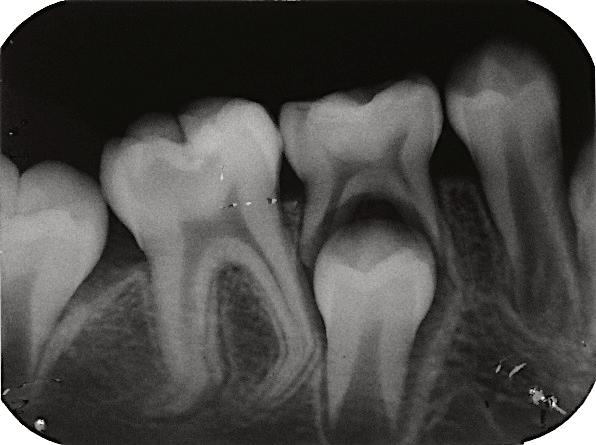

8.Biodentine®AnalternativeinVitalPulpTherapyinYoungPermanentTeeth.ClinicalCase,40monthFollow-Up. (Pgs.88-96)

Biodentine®UnaalternativaenlaTerapiaPulparVitalenDientesPermanentesJóvenes.CasoClínico.Seguimientode40Meses.

LuisDavidRamosFlores,DDS,